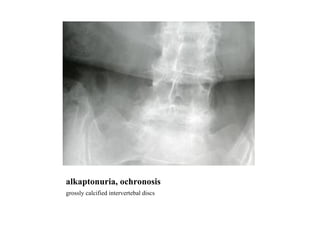

alkaptonuria, ochronosis grossly calcified intervertebal discs

alkaptonuria, ochronosis grosslycalcified intervertebal discs